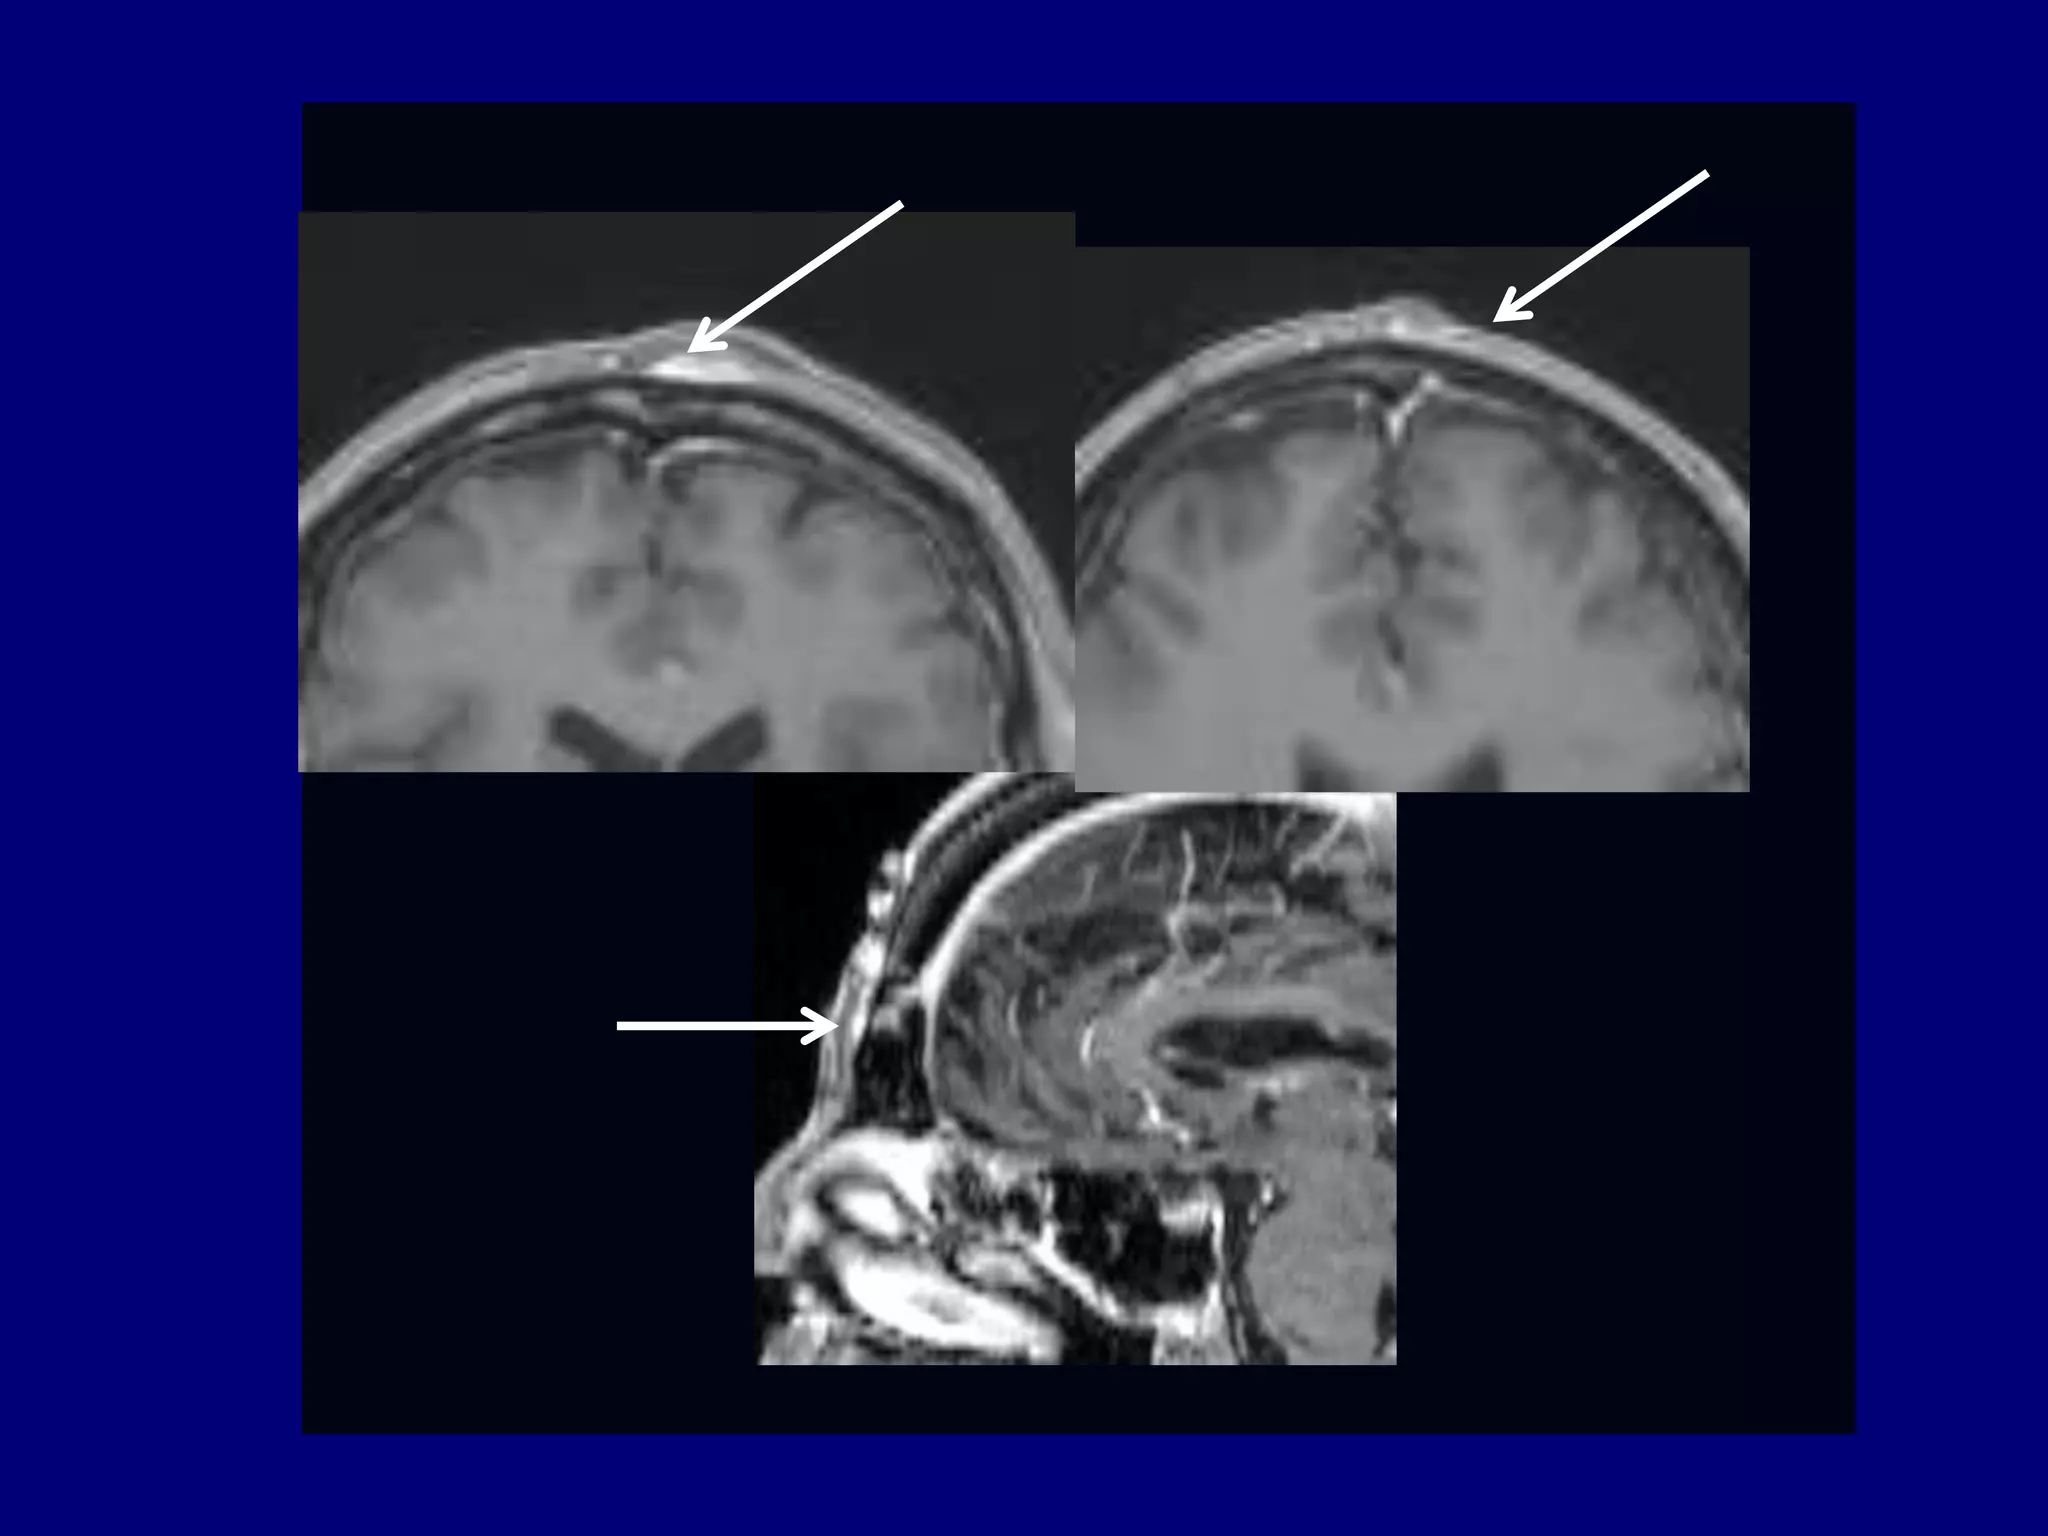

MRI 2012

T1-weighted post-gadolinium

MRI 2013

T2-weighted

FLAIR

Pre-operative Study

Pre-operative MRI T1-weighted post-gadolinium

Based on MR features,

surgery was cancelled and a

diagnostic Ultrasound was

performed